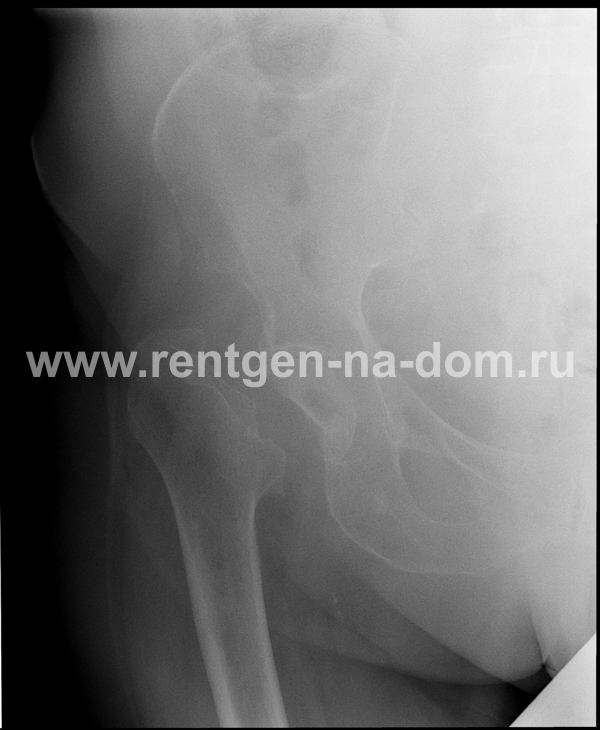

Перелом шейки бедренной кости.

Решающее значение в установлении диагноза перелома шейки бедра имеет рентгенография тазобедренного сустава. У пожилых пациентов приведенные выше симптомы могут проявляться нечетко, а такие заболевания как инсульт или невропатия, вообще, не позволят поставить правильный диагноз без рентгена. Где сделать рентген? Перелом шейки бедра всегда сопровождается сильной болью, поэтому любые лишние движения оборачиваются новыми мучениями, а сопутствующие заболевания внутренних органов усугубляют ситуацию! Решение есть - воспользоваться уникальной услугой – цифровой рентген на дому. К вам приедет врач рентгенолог-травматолог, который выполнит весь комплекс лечебно-диагностических мероприятий и подробно расскажет, что делать дальше.

Получение качественных рентгеновских снимков на дому предъявляет серьёзные требования к рентгеновской аппаратуре. Далеко не каждый переносной рентгенаппарат позволяет получать снимки необходимого качества, чтобы достоверно поставить диагноз. Используемый нами рентгенаппарат АРА 110/160 в комплексе с компьютерным радиографом позволяет получать цифровые рентгеновские снимки высокого качества у пациентов различной комплекции и является уникальной услугой в Санкт-Петербурге, предоставляемой на дому.